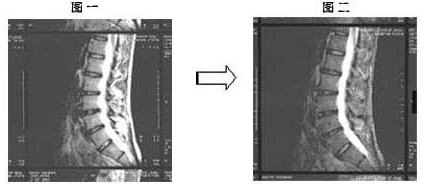

症状としては、一年程前に突然の腰痛で動けなくなり、整形外科を受診した結果、腰部椎間板ヘルニアと診断を受ける。診断後、牽引治療、抗炎症剤投与等の治療を受けるも効果はみず、これまで勤務していた自動車工場での勤務を断念し、一年間の休職に入る。その後、2003年の 3月に当院を受診、MRI【図1参照】で椎間板ヘルニアと診断。これまでの治療経緯を確認した上で、患者本人の合意を得て、バイオシャーク粉末 7.5g/1日での治療を開始した。

初診時の2003年 3月のMRI【図1参照】と2004年 4年のMRI【図2参照】を比較すると、椎間板の間の軟骨の回復がはっきりと見られ、ヘルニアの所見は改善したと診断できます。

椎間板の場合は、軟骨の再生という表現は適切ではないですが、軟骨が正常な弾力を取り戻したと考えられます。また、一ヶ月、二ヶ月後と痛みが減少し、消失している事からもヘルニアの症状に対しても、鎮痛効果があると考えられます。

约一年前因突然腰关节痛和坐骨神经痛导致无法行动,在整型外科诊断出罹患腰椎间盘突出症。之后,接受牵引治疗,服用抗炎药物等治疗方法,但始终未见成效。在那样情况下,该病患只好放弃汽车工厂的工作,办理停职一年。之后,2003年3月到本院接受诊疗,利用MRI(核磁共振图)(参看图一)诊断出腰椎间盘突出症。在确认该病患之前所接受的治疗经过后,得到患者本人同意,开始改以每日服用7.5g 百傲鲨锯峰齿鲛软骨粉末的治疗方式。

2003年3月初诊时的MRI(核磁共振图)(参看图一)与2004年4月的MRI(核磁共振图)(参看图二)相比,可清楚看到腰椎间盘突出症状,已有明显的改善。

椎间盘的场合,用软骨再生来表达不太合适,但可知软骨已恢复了正常弹性。而且,服用一个月后腰关节痛和坐骨神经痛感减少,两个月后疼痛状况完全消失,由此可得知百傲鲨对腰椎间盘突出症,具有消除坐骨神经痛和腰腿关节痛的效果。